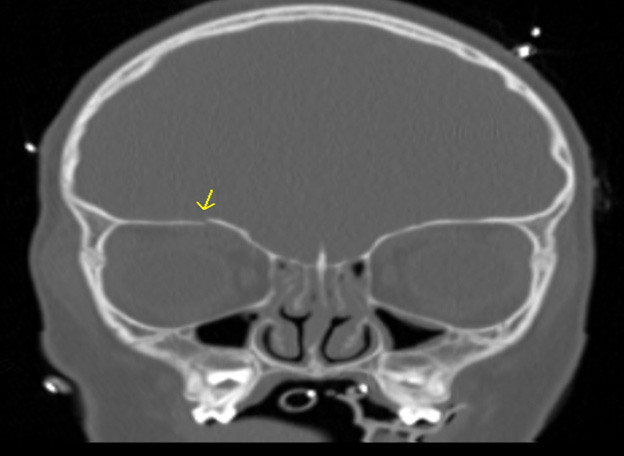

Figure 3 shows an example of an orbital roof fracture in a pediatric patient in the coronal plane. The image demonstrates a mildly displaced fracture.

Figure 3. Orbital Roof Fracture |

The image demonstrates a mildly displaced orbital roof fracture. Image courtesy of Mantosh S. Rattan, MD, Radiologist, Orlando Health Arnold Palmer Children’s Hospital, Orlando, FL. |